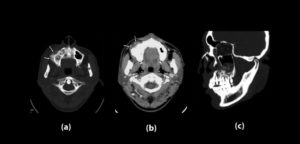

86 – Exactitud de los diferentes tipos de diseño de las guías quirúrgicas en la colocación de implantes

El número de pacientes que requieren prótesis sobre implantes ha aumentado considerablemente en los últimos años. La osteointegración de los implantes dentales es el requisito